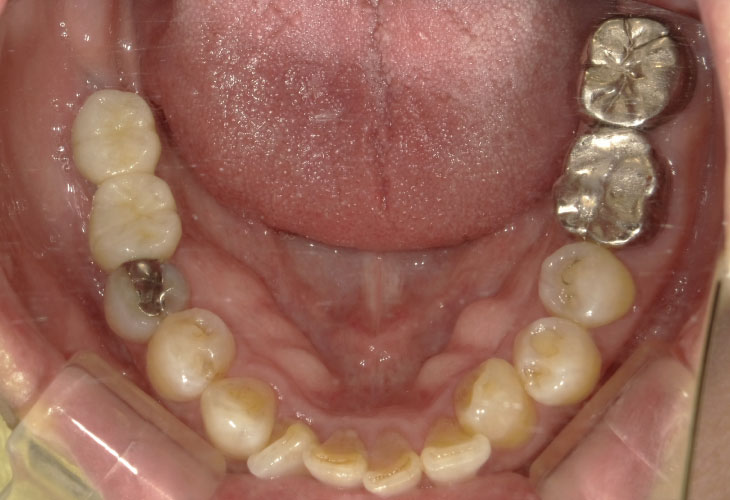

インプラント埋入(右上4・6,左上4・6,右下6,左下6) ジルコニアBr(右上3―左上3) ジルコニア(右下5,左下5) …続きを見る